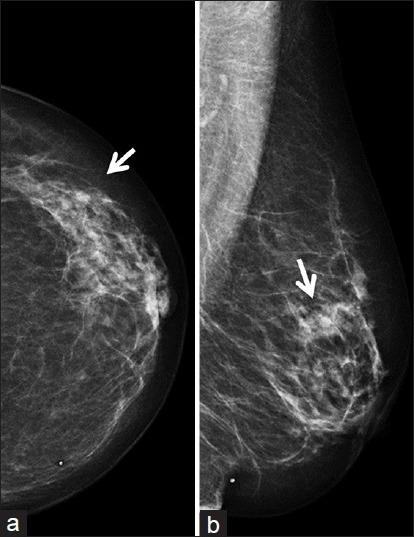

Metastatic tumors are rare in the breast. Well-differentiated neuroendocrine tumors (WDNETs) are slow-growing neoplasms that arise from neuroendocrine cells, particularly in the gastrointestinal tract and bronchial tree. Metastatic WDNET to the breast is a rare entity. We present a case report of ileal WDNET metastatic to the breast which was initially identified as a small mass in the patient's left breast on screening mammography. Targeted ultrasound identified a suspicious mass, and ultrasound-guided percutaneous core biopsy was performed. Pathology revealed metastatic WDNET. Breast magnetic resonance imaging (MRI) was then performed and demonstrated left axillary Level 2 lymphadenopathy, and liver lesions were suspicious for metastasis. The patient underwent abdominal computed tomography (CT) to evaluate for distant metastatic disease. A spiculated mass was found near the ileocecal valve, suggestive of primary ileal WDNET. In addition, CT identified multiple liver lesions, most compatible with metastasis. Indium 111 OctreoScan confirmed radiotracer uptake in the ileum consistent with primary neuroendocrine tumor. In this report, we review the imaging characteristics of metastatic WDNET to the breast by different imaging modalities including mammogram, ultrasound, and breast MRI.

转移性肿瘤在乳腺中较为罕见。高分化神经内分泌肿瘤(WDNETs)是起源于神经内分泌细胞的生长缓慢的肿瘤,尤其多见于胃肠道和支气管树。乳腺转移性WDNET是一种罕见的情况。我们报告一例回肠WDNET转移至乳腺的病例,该病例最初在乳腺钼靶筛查时被发现为患者左乳的一个小肿块。靶向超声检查发现一个可疑肿块,并进行了超声引导下经皮穿刺活检。病理结果显示为转移性WDNET。随后进行了乳腺磁共振成像(MRI)检查,结果显示左侧腋窝2级淋巴结肿大,肝脏病变可疑为转移灶。患者接受了腹部计算机断层扫描(CT)以评估远处转移情况。在回盲瓣附近发现一个有毛刺的肿块,提示原发性回肠WDNET。此外,CT检查发现多个肝脏病变,最符合转移表现。铟111奥曲肽扫描证实回肠有放射性示踪剂摄取,与原发性神经内分泌肿瘤一致。在本报告中,我们通过不同的成像方式,包括乳腺钼靶、超声和乳腺MRI,回顾了乳腺转移性WDNET的影像学特征。